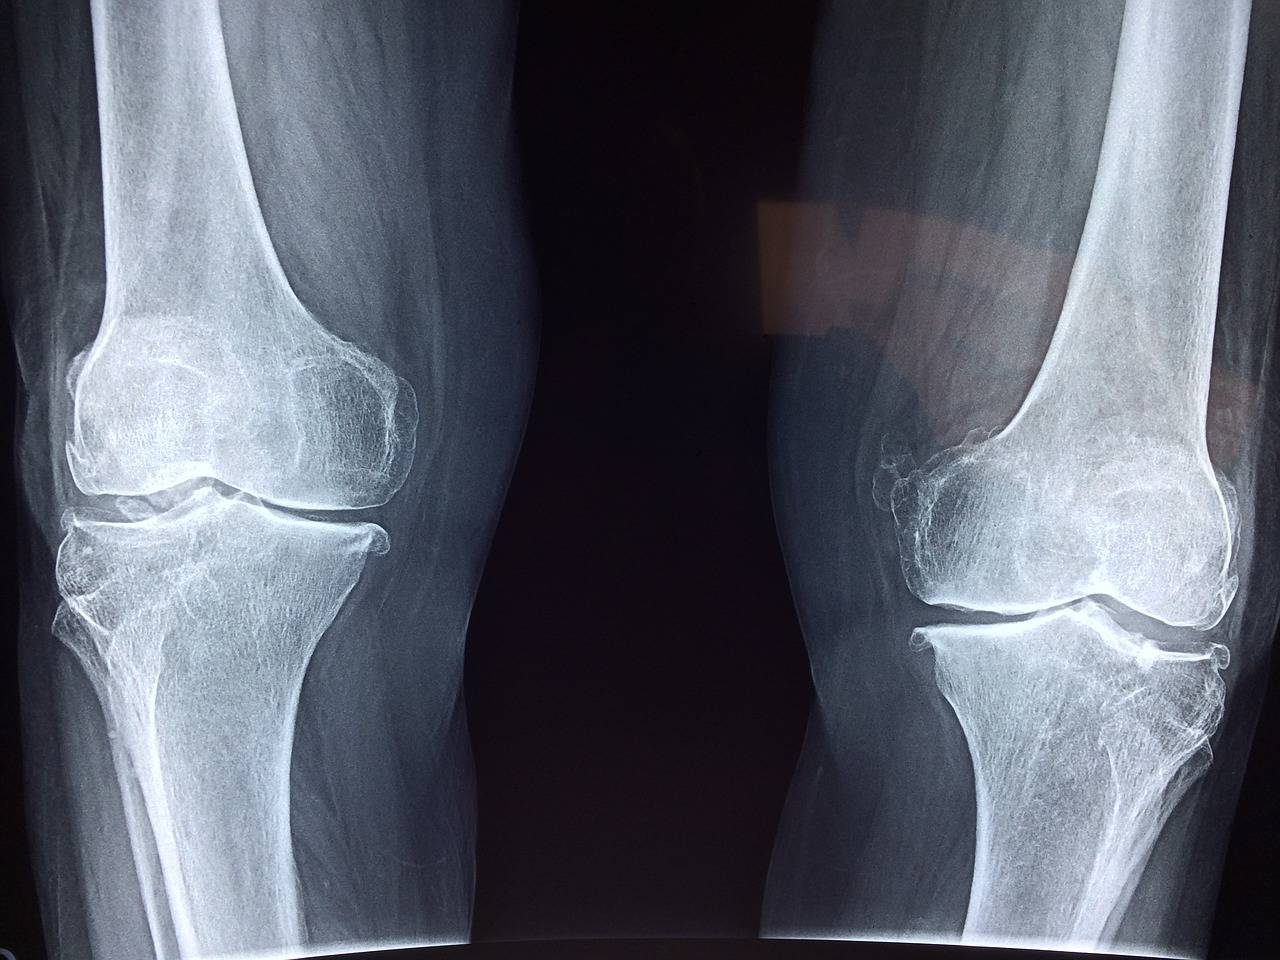

Entorse du genou - Rupture du LCA

Lésion ligamentaire après entorse du genou

Le ligament croisé antérieur de votre genou est abîmé, suite à une blessure. Il s’agit d’une traumatologie fréquente particulièrement au cours d’accidents sportifs ... La rupture du ligament croisé antérieur (LCA) a des conséquences graves pour l'athlète car l'instabilité du genou peut les empêch...